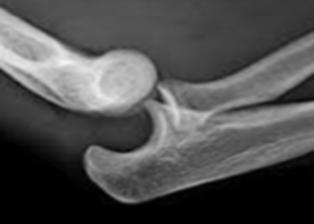

La luxación posterior es la más frecuente, sobre todo, en niños y la segunda luxación más frecuente en el adultos después de la luxación de hombro.

Dolor, impotencia, deformidad en forma de hachazo tricipital. También genera rigidez e inestabilidad. Deformación del triángulo de Nelaton. Puede lesionar el nervio mediano